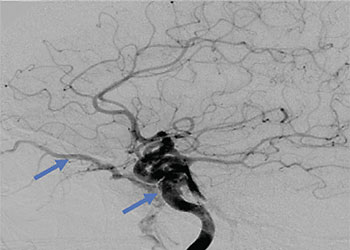

Collateral venous drainage into the orbit and skull base was observed (Figure A). After successful cannulation of the direct aperture between the right carotid artery and the cavernous sinus, balloon-assisted coil embolization of the posterolateral compartment was performed until the fistula was closed (Figure B and C). He experienced immediate cessation of his pulsatile tinnitus with an early improvement of the right VI nerve palsy and near-complete recovery of his vision within 6 weeks

Figure: (A) Right ICA Cavernous Fistula with Venous Shunting (B) Balloon Assisted Coil Embolization (C) Fistula Cured Post Embolization